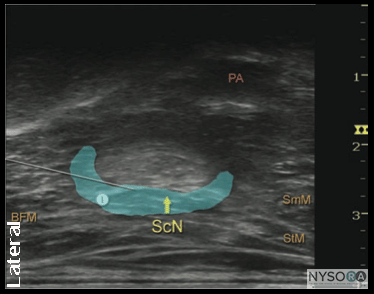

![]() Figure 7: Simulated needle path and the proper needle tip placement to block the sciatic nerve (ScN) through the lateral approach. BFM - Biceps femoris muscle, SmM - Semimembranosus muscle. StM - Semitendinosus muscle, PA- Popliteal artery. Technique With the patient in the proper position, the skin is disinfected and the transducer positioned to identify the sciatic nerve (Figure 5). If the nerve is not immediately apparent, tilting the transducer proximally or distally can help improve the contrast and bring the nerve "out" of the background (Figure 6). Alternatively, sliding the transducer slightly proximally or distally may improve the quality of the image and allow for better visualization. Once identified, a skin wheal is made on the lateral aspect of the thigh 2 to 3 cm above the lateral edge of the transducer. Then the needle is inserted in-plane in a horizontal orientation from the lateral aspect of the thigh and advanced toward the sciatic nerve (Figure 7). If nerve stimulation is used (0.5 mA, 0.1 msec), the contact of the needle tip with the sciatic nerve usually is associated with a motor response of the calf or foot. Once the needle tip is witnessed adjacent to the nerve, and after careful aspiration, 1 to 2 mL of local anesthetic is injected to confirm the proper injection site. Such injection should result in distribution of the local anesthetic within the epineural sheath, and often, separation of the TN and CPN. When injection of the local anesthetic does not appear to result in a spread around the sciatic nerve (Figure 8), additional needle repositions and injections may be necessary. When injecting into the epineurium, correct injection is recognized as local anesthetic spread proximally and distally to the site of the injection around both divisions of the nerve. This typically results in separation of TN and CPN during and after the injection.